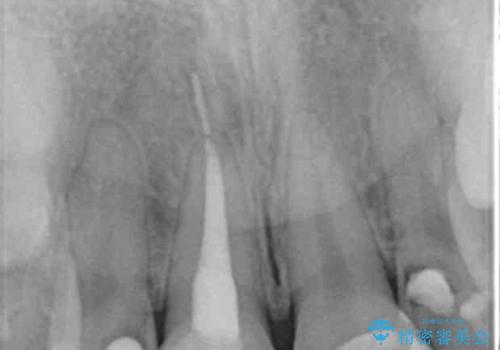

- 子供の頃にジュースが原因で虫歯が多発し、レジン修復をしていたが見た目の改善を希望され来院されました。

レジン充填・虫歯を丁寧に全て除去したのちジルコニアセラミックを用いた前歯の審美改善を計画します。